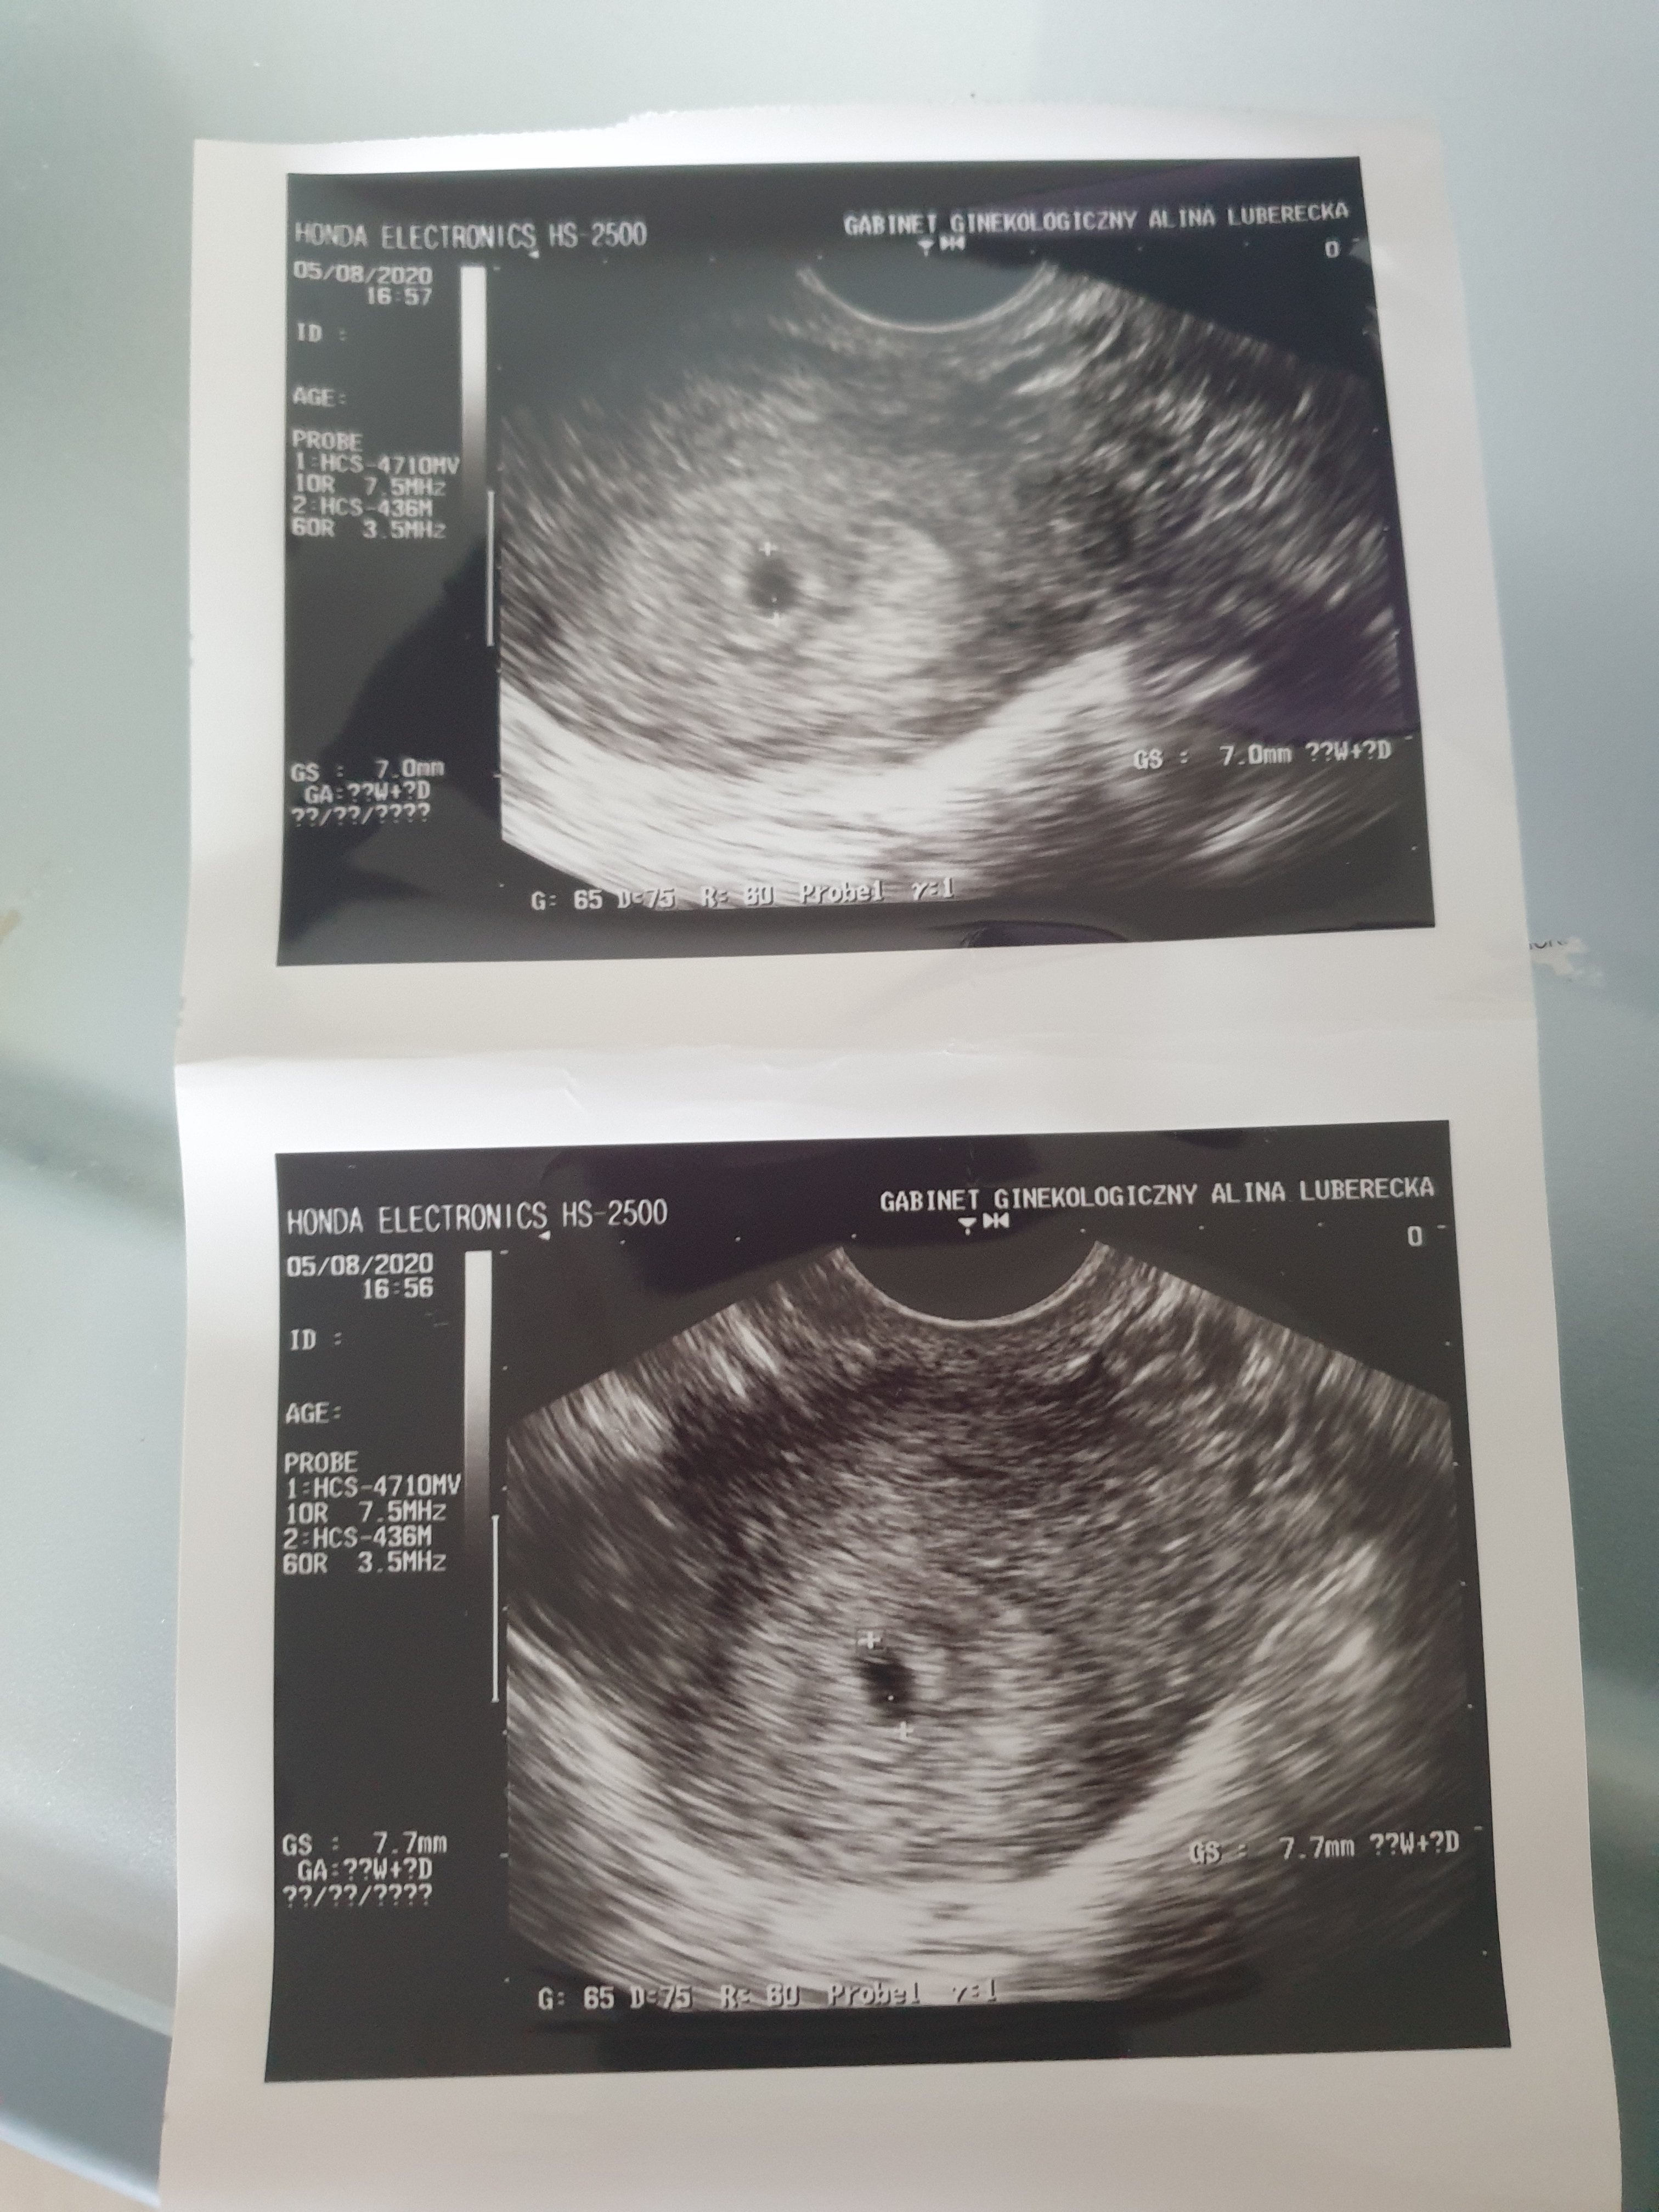

Tydzień temu w czwatek, 30.07 zrobilam test ciążowy-2 kreseczki. Ostatnia miesiączka 29.06 więc książkowo powinnam być aktualnie w 6 tygodniu ciąży. Od dnia spodziewanej miesiączki mocno boli mnie brzuch jak na okres stąd wczorajsza wizyta u Pani ginekolog która potwierdziła ciążę, jednak stwierdzila że jest ona malutka jak na swoj wiek bo pęcherzyk ciążowy ma wielkość 7.7mm .

Wrzucam usg choć z niego tak na prawde nic oprócz wielkosci pęcherzyka nie wynika. :/ Laboratorium mam otwarte też w sobotę, więc chyba jutro pojde na pierwszy pomiar bety, a w poniedzialek na kolejny, wiec moze coś więcej się wyjaśni.

Możesz wrzucić USG gdzie maluch jest widoczny ? Spojrzałam teraz na moje usg i wg miesiączki miał być to 6+1 tc, a na USG wyszło 6+4, a młody miał 0,71 cm więc był mniejszy niż twój.